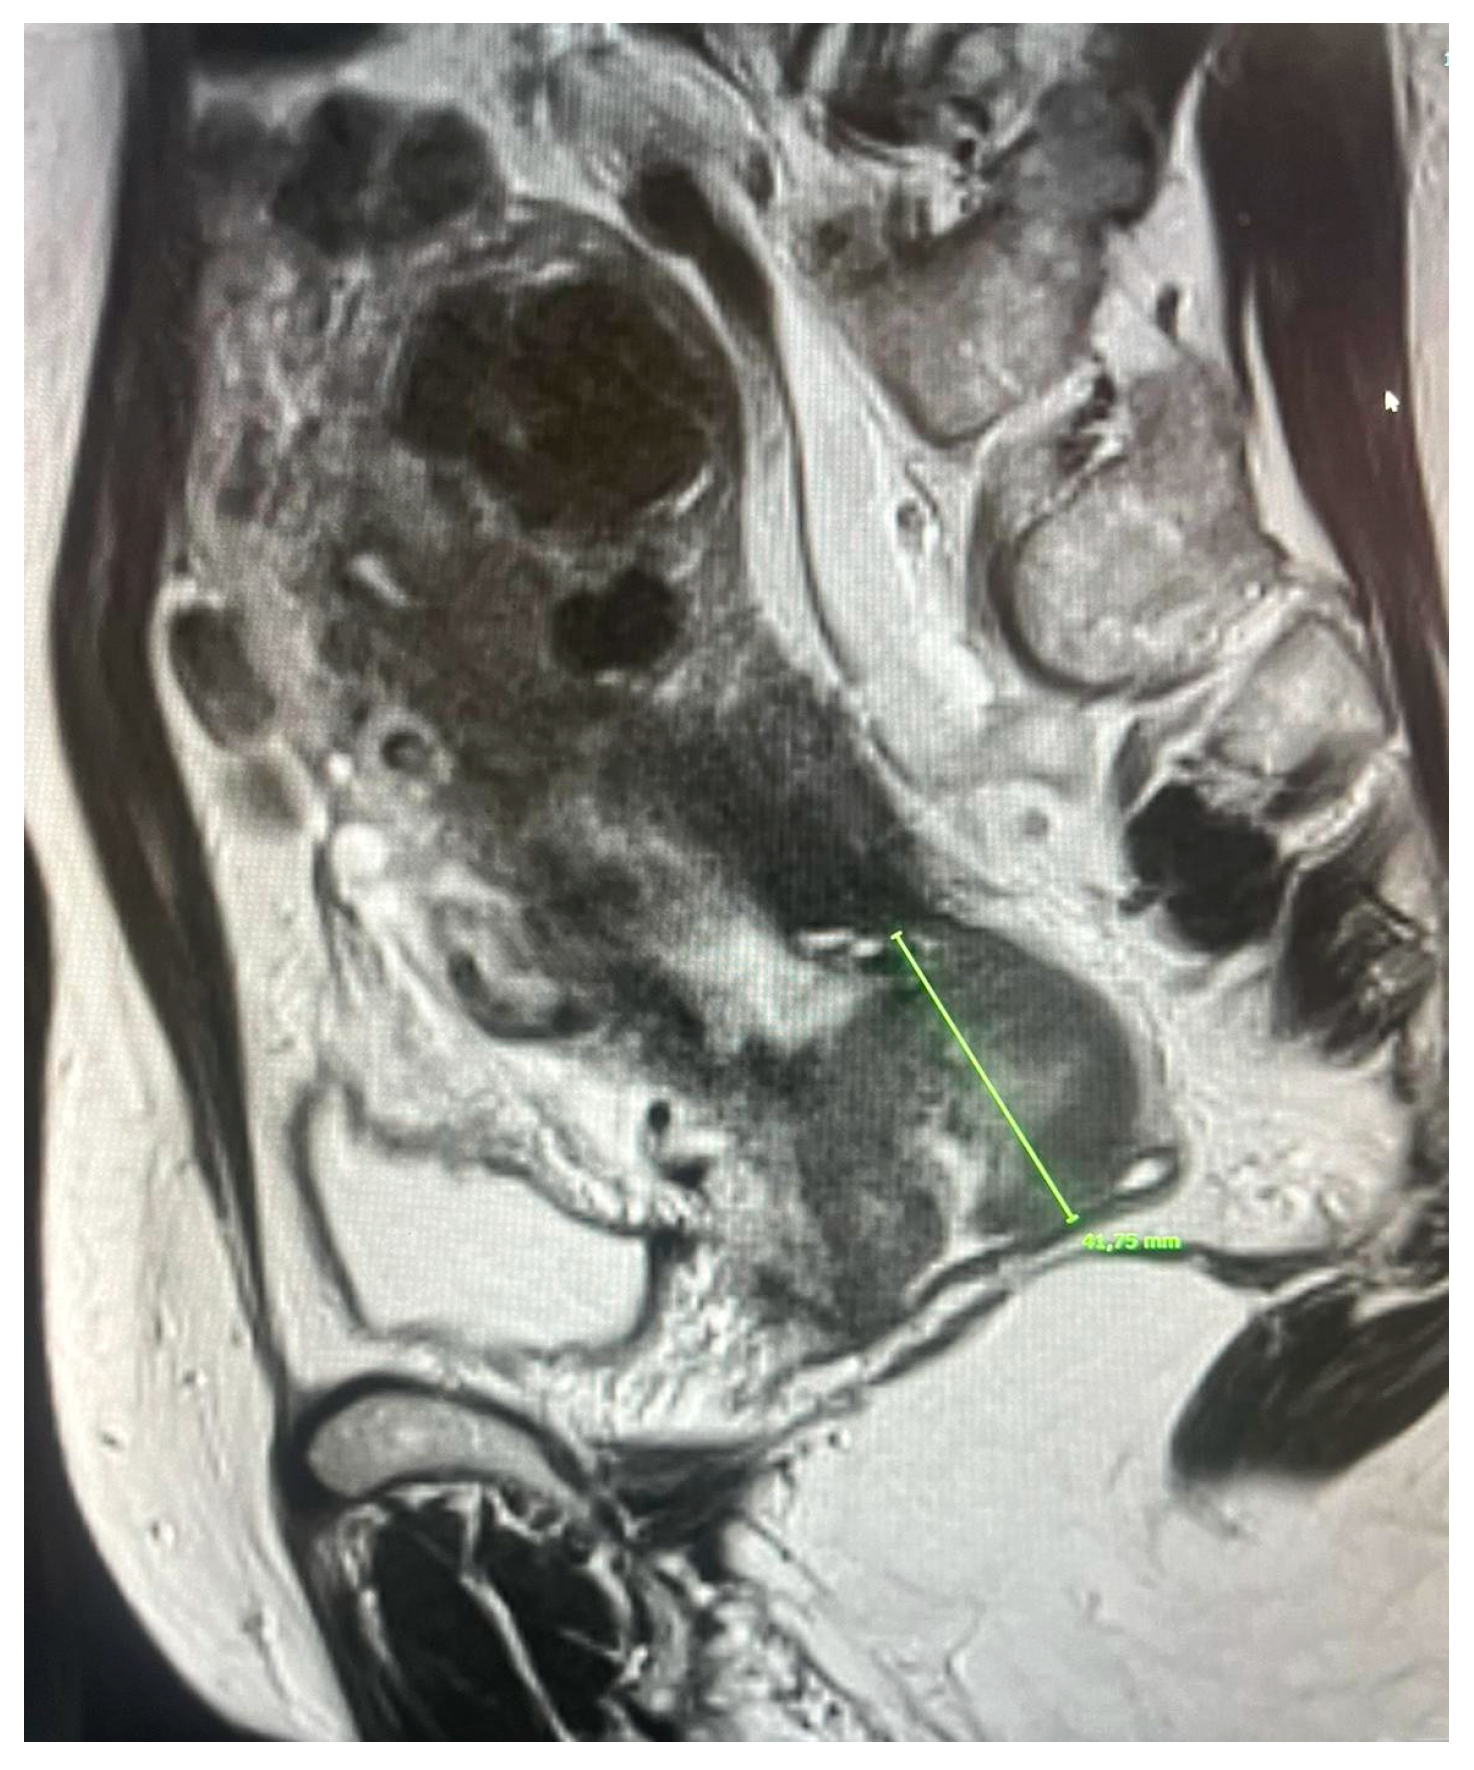

3.3. Stage IIIA–Extension to the Lower Third of the Vagina

In the 2018 FIGO classification, lower vaginal third involvement defines stage IIIA and leads to a worsening prognosis, as well as a notable change in treatment planning. Correct identification of this condition is therefore crucial to avoid staging errors and appropriately plan treatment.

Traditional clinical examination and transvaginal ultrasound have shown limitations in terms of sensitivity and specificity, especially in cases of bulky tumors or in the presence of bleeding. Multiparametric MRI, thanks to the tissue contrast of T2-weighted sequences, has proven superior. Under normal conditions, the vaginal wall appears as a thin, hypointense line on T2, separating the mucosa from the surrounding environment. Its loss or interruption is the key sign of tumor infiltration [30,31]. However, this finding can be distorted by inflammatory processes or motion artifacts, which is why integration with functional sequences is now considered essential.

Prospective studies have confirmed the accuracy of this method. Pálsdóttir et al. (2021) reported a specificity of 96% and a higher overall accuracy compared to transvaginal ultrasound (96% vs. 83%) [23]. Similarly, Zhu et al. (2021) showed that MRI achieves a specificity of 92%, compared to 80% for ultrasound, with a significant advantage in tumors that diffusely infiltrate the vaginal wall [22].

Other methods have also been compared with MRI. Vaginosonography, studied by Vidal Urbinati et al. (2022), showed a sensitivity and specificity of around 89%, demonstrating a fair degree of accuracy especially in small tumors [37]; however, MRI maintained an advantage in bulky cases, where ultrasound assessment is more complex.

The literature agrees that mpMRI is the reference technique for assessing vaginal extension, both for its ability to distinguish lower third involvement (crucial for staging) and for its ability to precisely define the length and volume of the disease. This information is essential not only for staging purposes but also for brachytherapy planning, where accurate delineation of the vaginal extension allows for more precise design of target volumes. Clinically, involvement of the lower third of the vagina leads to caudal extension of external beam radiation fields, potentially impacting late-stage morbidity, particularly sexual functioning and quality of life. Accurate assessment of vaginal extension is therefore essential not only for correct staging but also for adequate treatment planning.

Functional sequences may further contribute. Specifically, DWI has been proposed to increase sensitivity in cases where T2 assessment is uncertain, while DCE may provide clues to infiltration based on an early mucosal enhancement pattern. These parameters, although not yet fully validated on a large scale, could contribute to further improving diagnostic accuracy in the future.

In conclusion, MRI represents the most reliable method for assessing vaginal extension, with superior performance compared to transvaginal ultrasound and vaginosonography, and with a direct impact on correct staging and treatment planning (Figure 3).